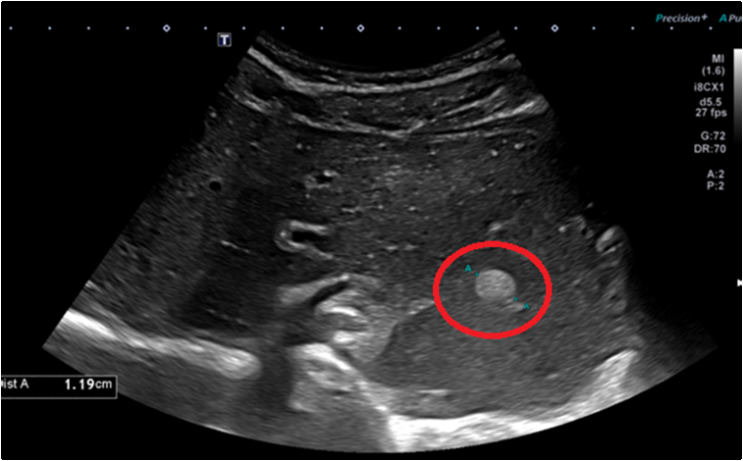

방치하면 치료 가능성이 줄고, 선택 가능한 치료 방식(수술, 고주파열치료 등)이 제한됩니다. 그래서 정기적인 검사, 특히 6개월마다 복부초음파와 혈액검사를 통한 간 기능/바이러스 수치 확인은 간의 건강을 지키는 효과적인 첫걸음입니다.

간암, 간염에 관련 사례를 확인하실 수 있습니다.